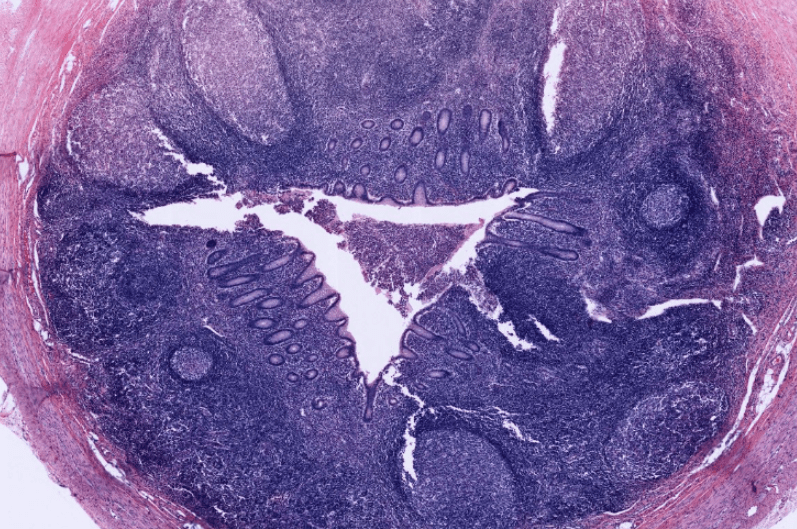

APÉNDICE

El revestimiento del apéndice es similar a la del colon.Esta se caracteriza por exhibir muchos nódulos linfoides en su lámina propia.El apéndice se origina como una evaginación del ciego.En ocasiones es posible observar adipocitos en la submucosa del apéndice.A diferencia del colon, la luz del apéndice es más reducida.La muscular externa del apéndice se conforma de una sola capa de músculo liso de manera longitudinal.Apéndice, HyE.Nódulo linfático secundario ubicado en la Lámina Propia (LP) del apéndice.